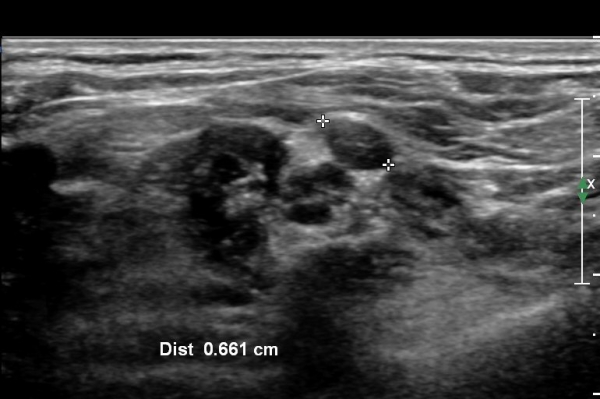

ŽÃËÀÚ¸¦ Á¶±Ý ¸»´ÜÀ¸·Î À̵¿ÇÏ¿© Àü»ç°¢±Ù°ú Á߻簢±Ù »çÀÌ¿¡¼­ »ó¿Ï½Å°æÃÑÀÇ Àú¿¡ÄÚ ºÎÁ¾ÀÌ °üÂûµÊ                  (»çÁø 2, 3).

¸ñ ¾Õ ¿ÜÃø¿¡¼­ Á¦5, 6 ½Å°æ±Ù Á¾´Ü¸é°Ë»ç¿¡¼­ Á¦5, 6 ½Å°æ±ÙÀÇ Àú¿¡ÄÚ ºÎÁ¾(4,5mm, 6.5 mm)ÀÌ

°üÂûµÇ°í »çÁø 4,5 ) °ÇÃø(»çÁø 6, 7)(2.4mm, 3.1mm)°ú ºñ±³ÇÏ¸é ¾à 2¹èÀÌ»ó ºÎÁ¾ÀÌ ¶Ñ·ÇÇÔ.